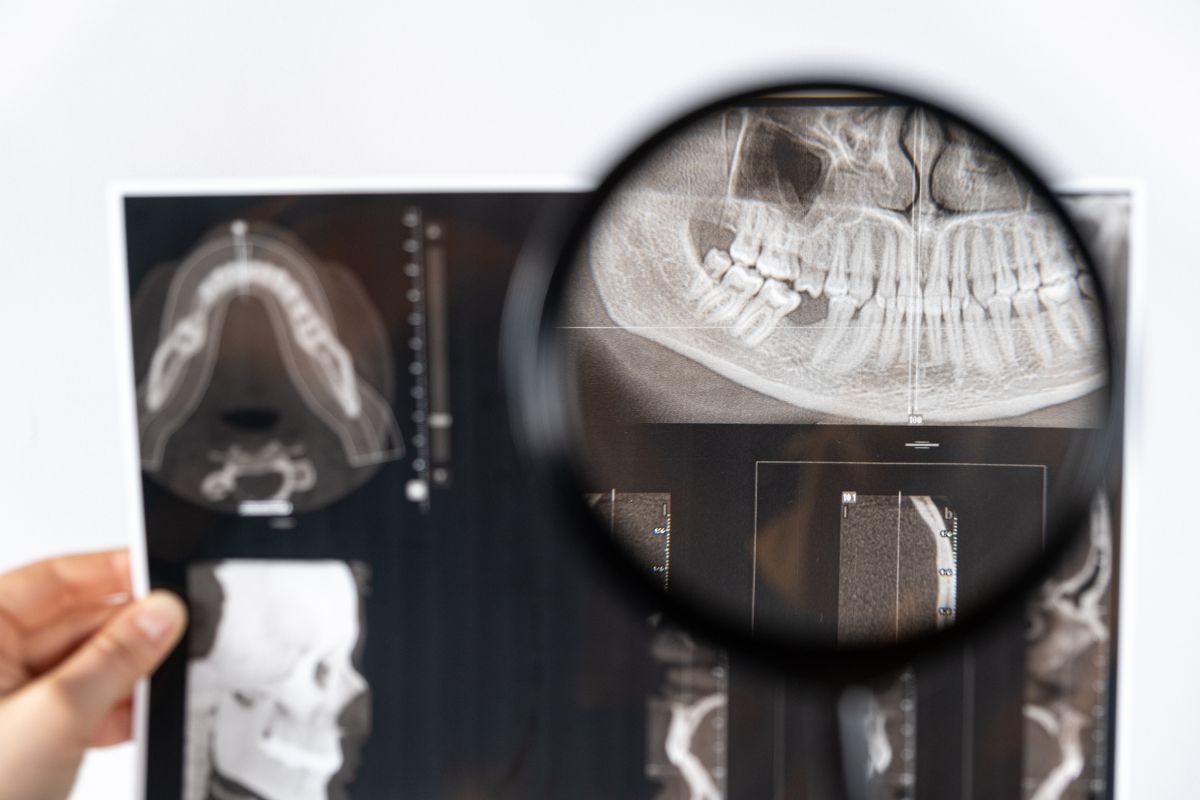

Diagnóstico de la ATM:

Un diagnóstico preciso es fundamental para el desarrollo de un plan de tratamiento efectivo para los trastornos de la ATM. Esto puede implicar una evaluación clínica completa, pruebas de imagen y, en algunos casos, pruebas de laboratorio.

La evaluación clínica incluirá un examen detallado de la mandíbula, la cabeza, el cuello y la cara, evaluando la amplitud de movimiento, la presencia de dolor o sensibilidad, y los sonidos asociados con el movimiento de la mandíbula.